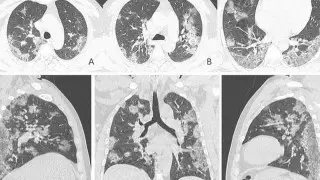

Одна из отличительных особенностей вирусной пневмонии - это симметричное поражение легких с полисегментарными воспалительными изменениями (в нескольких частях, то есть в разных долях и разных не смежных сегментах). Другие виды пневмонии развиваются, как правило, в пределах одной доли легкого, а не везде. Так, при заболевании COVID-19 на компьютерных томограммах видны уплотнения легочной ткани, похожие на прозрачные потертые пятна. В медицине такие патологии называют симптомом "матового стекла".

На ранней стадии развития вирусной пневмонии (проявляется до четвертого дня заболевания) "матовое стекло" возникает не более чем в трех очагах. При этом уплотнения распространяются преимущественно в нижних долях и по периферии, а их максимальный диаметр не превышает три сантиметра. Из-за повреждений в альвеолах скапливается жидкость, которая приводит к нарушению кислородного обмена и кислородному голоданию пациента, такие пациенты начинают жаловаться на одышку и затрудненность дыхания.

Затем пневмония начинает прогрессировать. В течение пяти-восьми дней количество уплотнений по типу "матового стекла" становится больше, и они постепенно трансформируются в очаги консолидации по периферии легких.

На пиковой стадии вирусной пневмонии (она развивается на 10–13-й день) появляются множественные уплотнения по типу "матового стекла" с различной протяженностью. Причем поражение может быть более обширным - субтотальным, с вовлечением всей доли целиком, а не только в пределах одного сегмента.